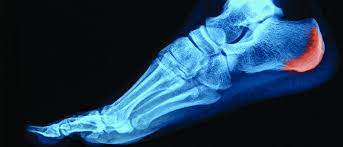

Hoy entrevistamos al Lic. Rodrigo Martínez, quien nos habla sobre: “Espolón calcáneo versus fascitis plantar” Contanos acerca de esto, lo que es la fascitis plantar, el espolón. ¿Se combinan los dolores, cómo es? Hay un estudio que yo estuve leyendo que...